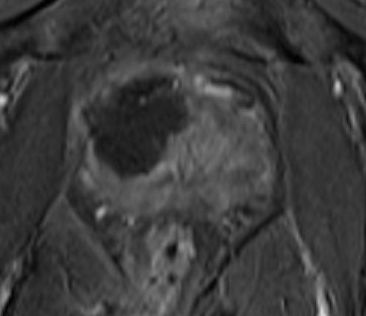

Below is my diagnostic MRI scan (September 2013), showing an "80% 1cc likely tumour" (Red areas on drawings)

My TPM Biopsy (as discussed in the video above) then confirmed it was localised prostate cancer (12mm Gleason 3+4).

The image below shows the cryo ablated (destroyed) area-

the

dark area. The

surgeon says "it looks very good", so I presume that means he ablated an ideal area.

(Remember: "left" in the image is the right hand side of my body)

I must say, the area ablated looks

much larger than the red area marked on my

first MRI. However, the surgeon did say that he would target an area a little larger than that, to be sure all the index lesion was killed off, plus I guess the precision of the cryo comes into play.